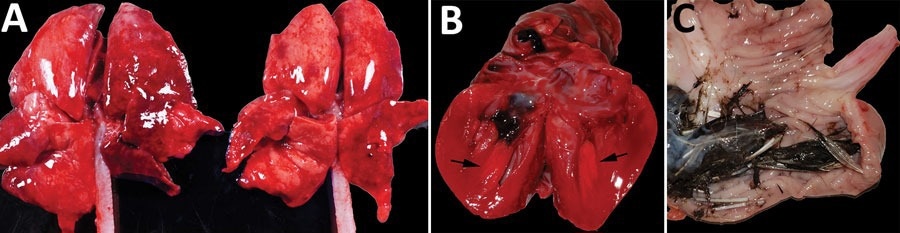

Gross photographs of postmortem lesions from red foxes naturally infected with highly pathogenic avian influenza virus, United States. A) Lungs have failed to collapse and are diffusely edematous and mottled pink to dark red. B) Cross section of the left ventricle of the heart showing a focal region of myocardial pallor in the papillary muscle (arrows). C) Stomach contents with feathers.

Dyspnea occurred in two skunks, a red fox and a bobcat. A gross post-mortem examination of 58 animals indicated that most had fair or good nutrition. Lung abnormalities were consistent, with hemorrhage and congestion being the most prevalent brain lesions. Others included pallor, congestion, hypertrophy, liver hemorrhage, and renal congestion with cortical hemorrhage. The team infrequently observed pericardial effusion, pallor, and petechia in the myocardial tissues.